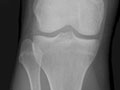

- Radiografías . Se obtienen imágenes de los huesos en una articulación, como la cadera o la rodilla, para determinar si hay daño en el cartílago.

- Artroplastia o reemplazo articular. Se realiza cuando otros tratamientos no han funcionado y el daño en la articulación puede verse en las radiografías. Incluye cirugía para reemplazar los extremos de los huesos en una articulación dañada. La cirugía crea nuevas superficies de la articulación. Las articulaciones que se reemplazan con más frecuencia son la cadera, la rodilla y el hombro. Pero también pueden reemplazarse otras articulaciones como el codo y el tobillo.

Si tiene las articulaciones sensibles e hinchadas y los músculos débiles, esto también ayudará a que su médico confirme si usted tiene artritis. Usted también podría tener que hacerse radiografías para revisar si tiene daño en las articulaciones. Es posible que su médico desee realizarle análisis de sangre u otras pruebas para determinar si existen otras causas por las que tiene dolor.